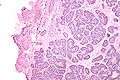

| Micrograph of a Sertoli cell nodule. H&E stain. | |

A Sertoli cell nodule, also Pick's adenoma, testicular tubular adenoma and tubular adenoma of the testis, is a benign proliferation of Sertoli cells that arises in association with cryptorchidism (undescended testis). They are not composed of a clonal cell population, i.e. neoplastic; thus, technically, they should not be called an adenoma.[1]

Sertoli cell nodules are unencapsulated nodules that consist of:[1][2]

- cells arranged in well-formed tubules (that vaguely resemble immature Sertoli cells), with

- bland hyperchromatic oval/round nuclei that are stratified, and

- may contain eosinophilic (hyaline) blob in lumen (centre).